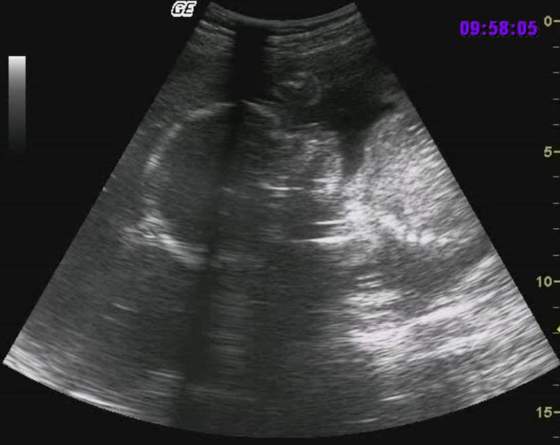

Kasiu skoro Twoj lekaz ma taki slaby sprzed moze tez skus sie na 3d aby zobaczyc czy z maluszkiem wszystko ok:-)